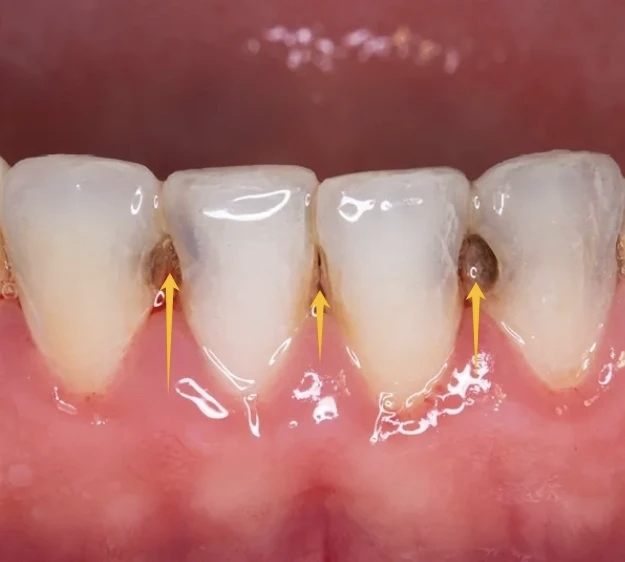

尤其是在夜间,唾液分泌减少,口腔的自洁能力变差,这种腐蚀作用会加倍,导致牙齿在不知不觉中迅速龋坏。这种情况在医学上被称为 “低龄儿童龋”或 “奶瓶龋” ,往往发展迅猛,从门牙开始,波及多颗牙齿。

医生解释:母乳和奶粉中的营养,同样也是口腔内细菌的“美食”。奶液中的糖分会残留在宝宝口腔和牙缝中。如果喝完不清洁,这些糖分就会被细菌分解成酸性物质,整夜地侵蚀牙齿。